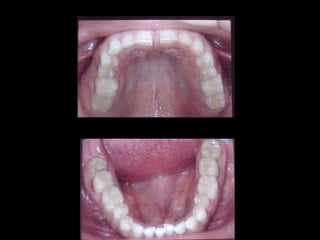

Modelos PreoperatoriosModelos Preoperatorios

Arcada Superior:

Forma oval

Paladar profundo

Totalidad de órganos dentarios a excepción de tercer molar izq.

Restauraciones deficientes

Arcada Inferior:

Forma ovalada

Colapso posterior

Ligero apiñamiento de anteriores

Rotación de premolares

Arcada Superior: Forma oval Paladarprofundo Totalidad de órganos dentarios a excepción de tercer molar izq. Restauraciones deficientes Arcada Superior: Forma oval Paladar profundo Totalidad de órganos dentarios a excepción de tercer molar izq. Restauraciones deficientes Frente: Línea media desviada Mordida cruzada anterior Frente: Línea media desviada Mordida cruzada anterior Arcada Inferior: Forma ovalada Colapso posterior Ligero apiñamiento de anteriores Rotación de premolares Arcada Inferior: Forma ovalada Colapso posterior Ligero apiñamiento de anteriores Rotación de premolares